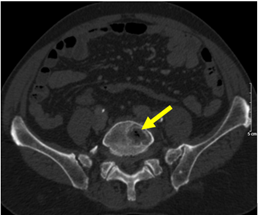

- Chụp CT bụng (tháng 9/2024): Ổ tiêu xương thân đốt sống L4-L5, theo dõi thứ phát

Hình 3: Ổ tiêu xương, phá hủy thân đốt sống L4-L5 (mũi tên vàng)

Hình 9: Hình ảnh CT bụng: hình ảnh tổn thương tiêu xương (mũi tên vàng) giảm bớt sau 6 đợt điều trị, xuất hiện hình ảnh đặc xương tại thân đốt sống (mũi tên đỏ)